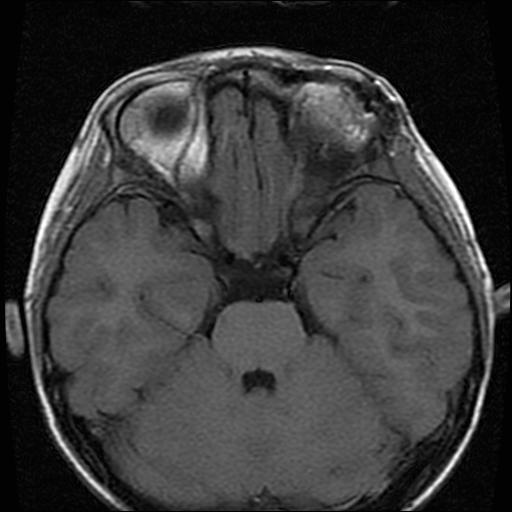

6岁小儿,左侧视神经瘤术后。现左侧视力减退。